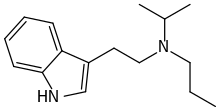

| PiPT | artificial | H | CH2CH2CH3 | CH(CH3)2 | N-Propyl-N-isopropyltryptamine | 1354632-00-0 |